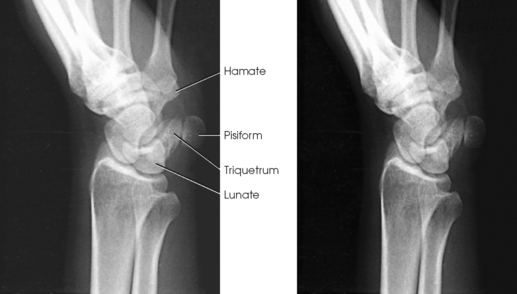

The wrist has eight carpal bones, which are fitted closely together and arranged in two horizontal rows (see Fig. 4-1). The carpals are classified as short bones and are composed largely of cancellous tissue with an outer layer of compact bony tissue. These bones, with one exception, have two or three names; this atlas uses the preferred terms (see box). The proximal row of carpals, which is nearest the forearm, contains the scaphoid, lunate, triquetrum, and pisiform. The distal row includes the trapezium, trapezoid, capitate, and hamate.

Each carpal contains identifying characteristics. Beginning at the proximal row of carpals on the lateral side, the scaphoid, the largest bone in the proximal carpal row, has a tubercle on the anterior and lateral aspect for muscle attachment and is palpable near the base of the thumb. The lunate articulates with the radius proximally and is easy to recognize because of its crescent shape. The triquetrum is roughly pyramidal and articulates anteriorly with the hamate. The pisiform is a pea-shaped bone situated anterior to the triquetrum and is easily palpated.

Structures shown: This position separates the pisiform from the adjacent carpal bones. It also provides a more distinct radiograph of the triquetrum and hamate (compare Figs. 4-81 and 4-82).